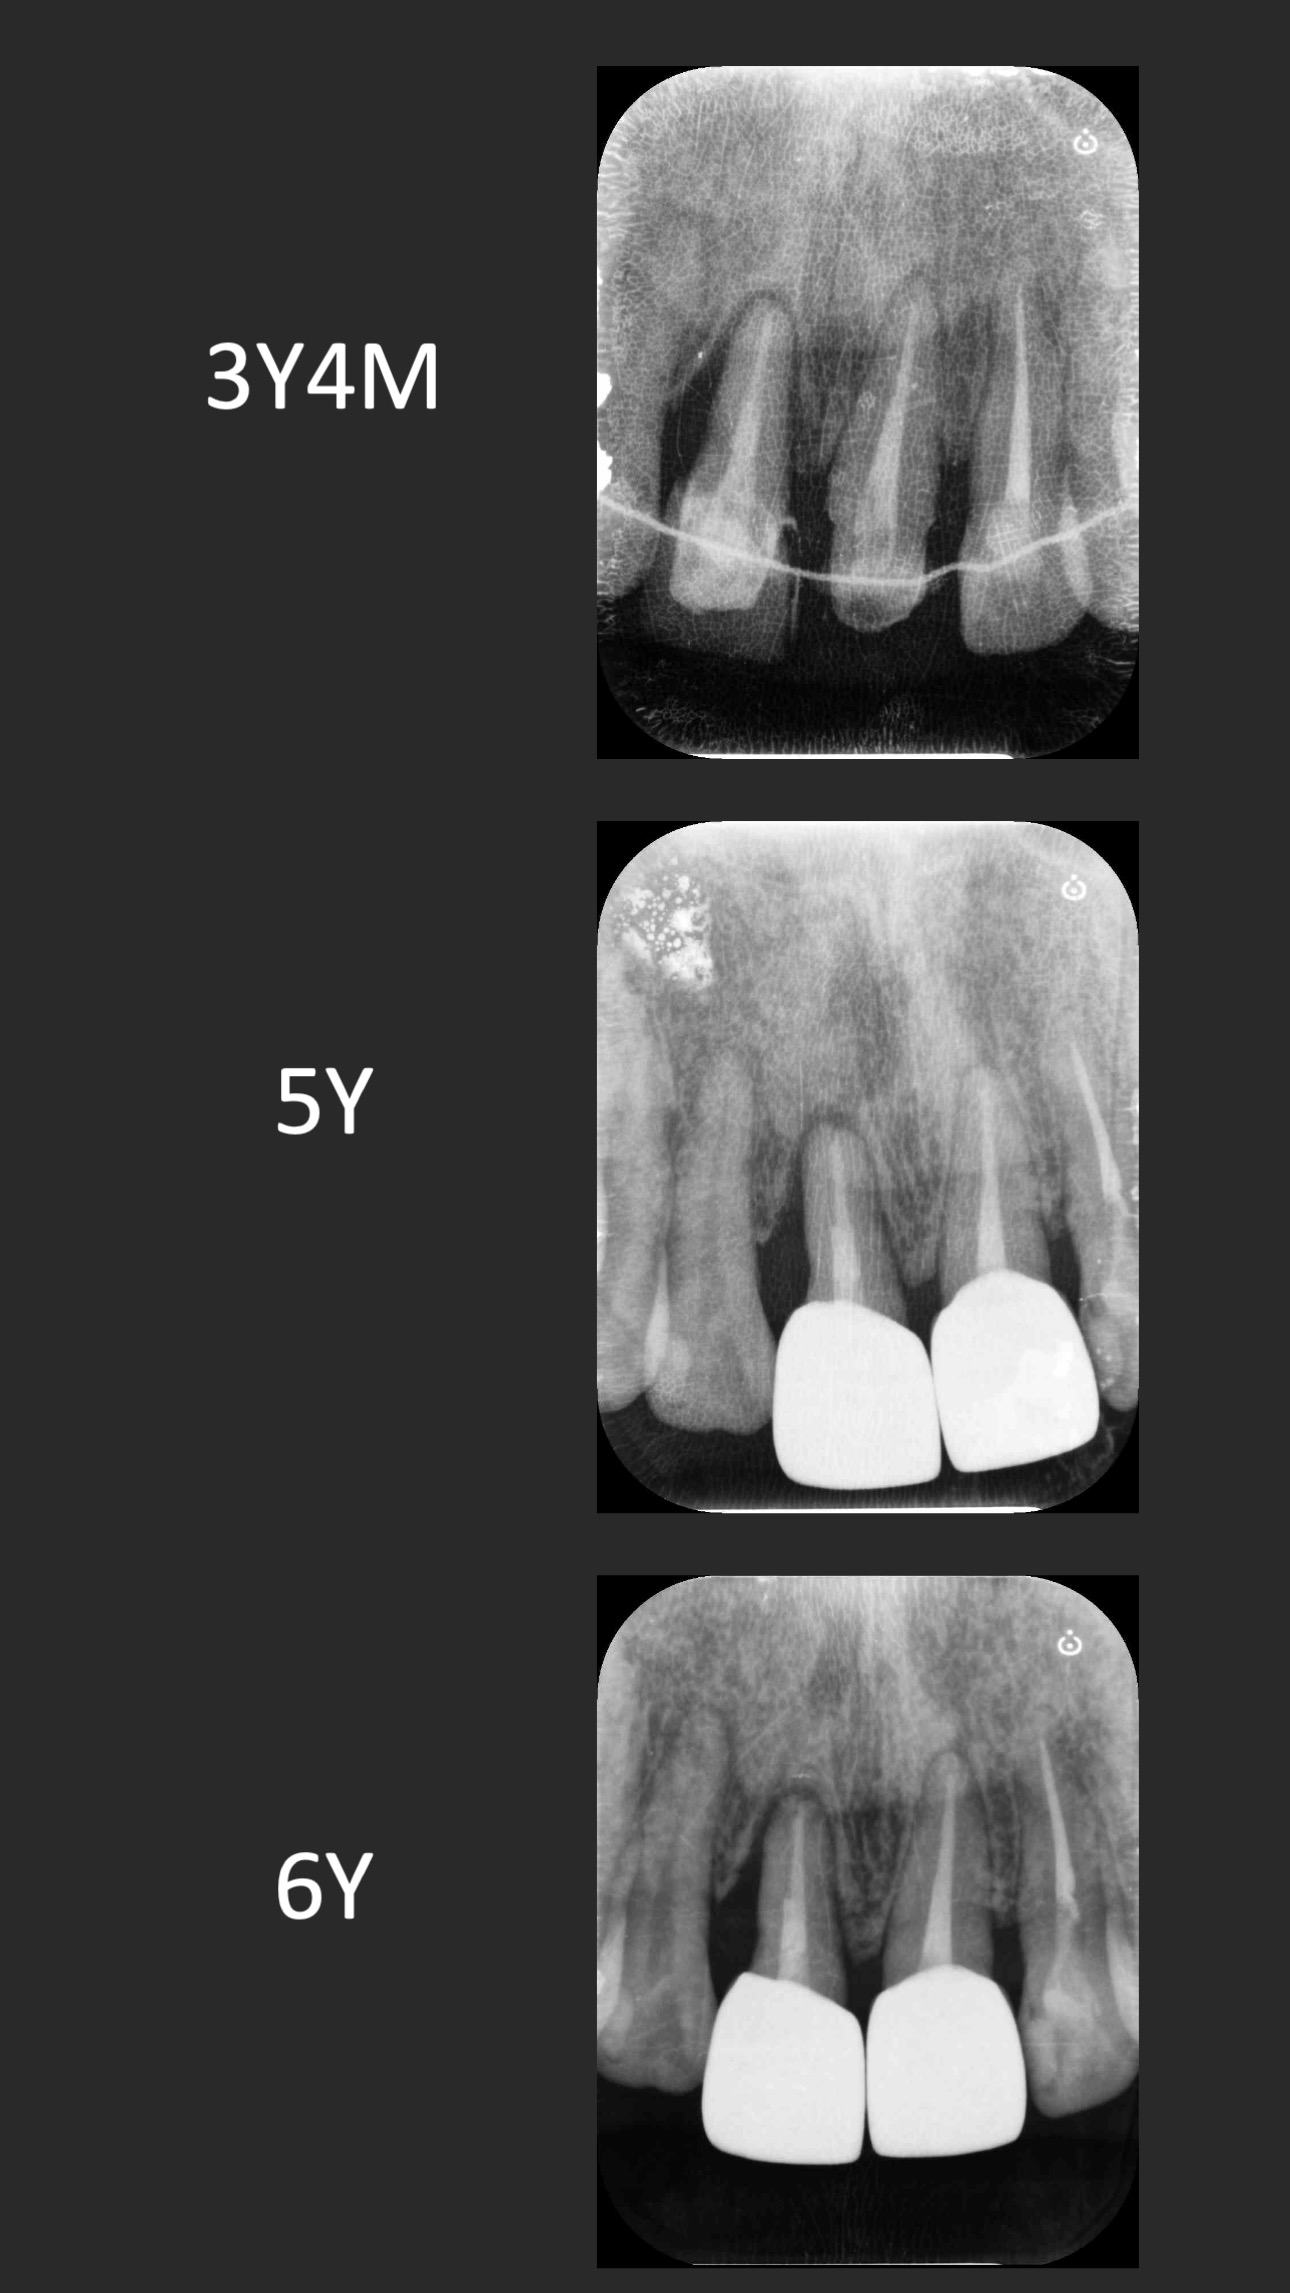

六年追蹤

這個案例,最早沒把握能救回來,但是做完非手術治療,發現恢復非常好。

於是大膽地請矯正與假牙專科醫師一起幫忙完成。其實病人本身也同意,若途中狀況不好,還是得拔除。我知道這種案例,其實對其他專科來說,可能是有壓力的,不容易處理,也是難症。

好佳在,兩位神隊友都完成了,非常感謝合作專科的信任,還有,病患六年來維持得非常好,目前囊袋正常、零出血、零發炎。

回頭看,一開始就拔掉牙齒,改走其他路線,或許也可以,每位醫師選擇的或許不一樣,並沒有標準答案。

但是,能幫病患留下自己的牙齒,真的是很開心的一件事~~